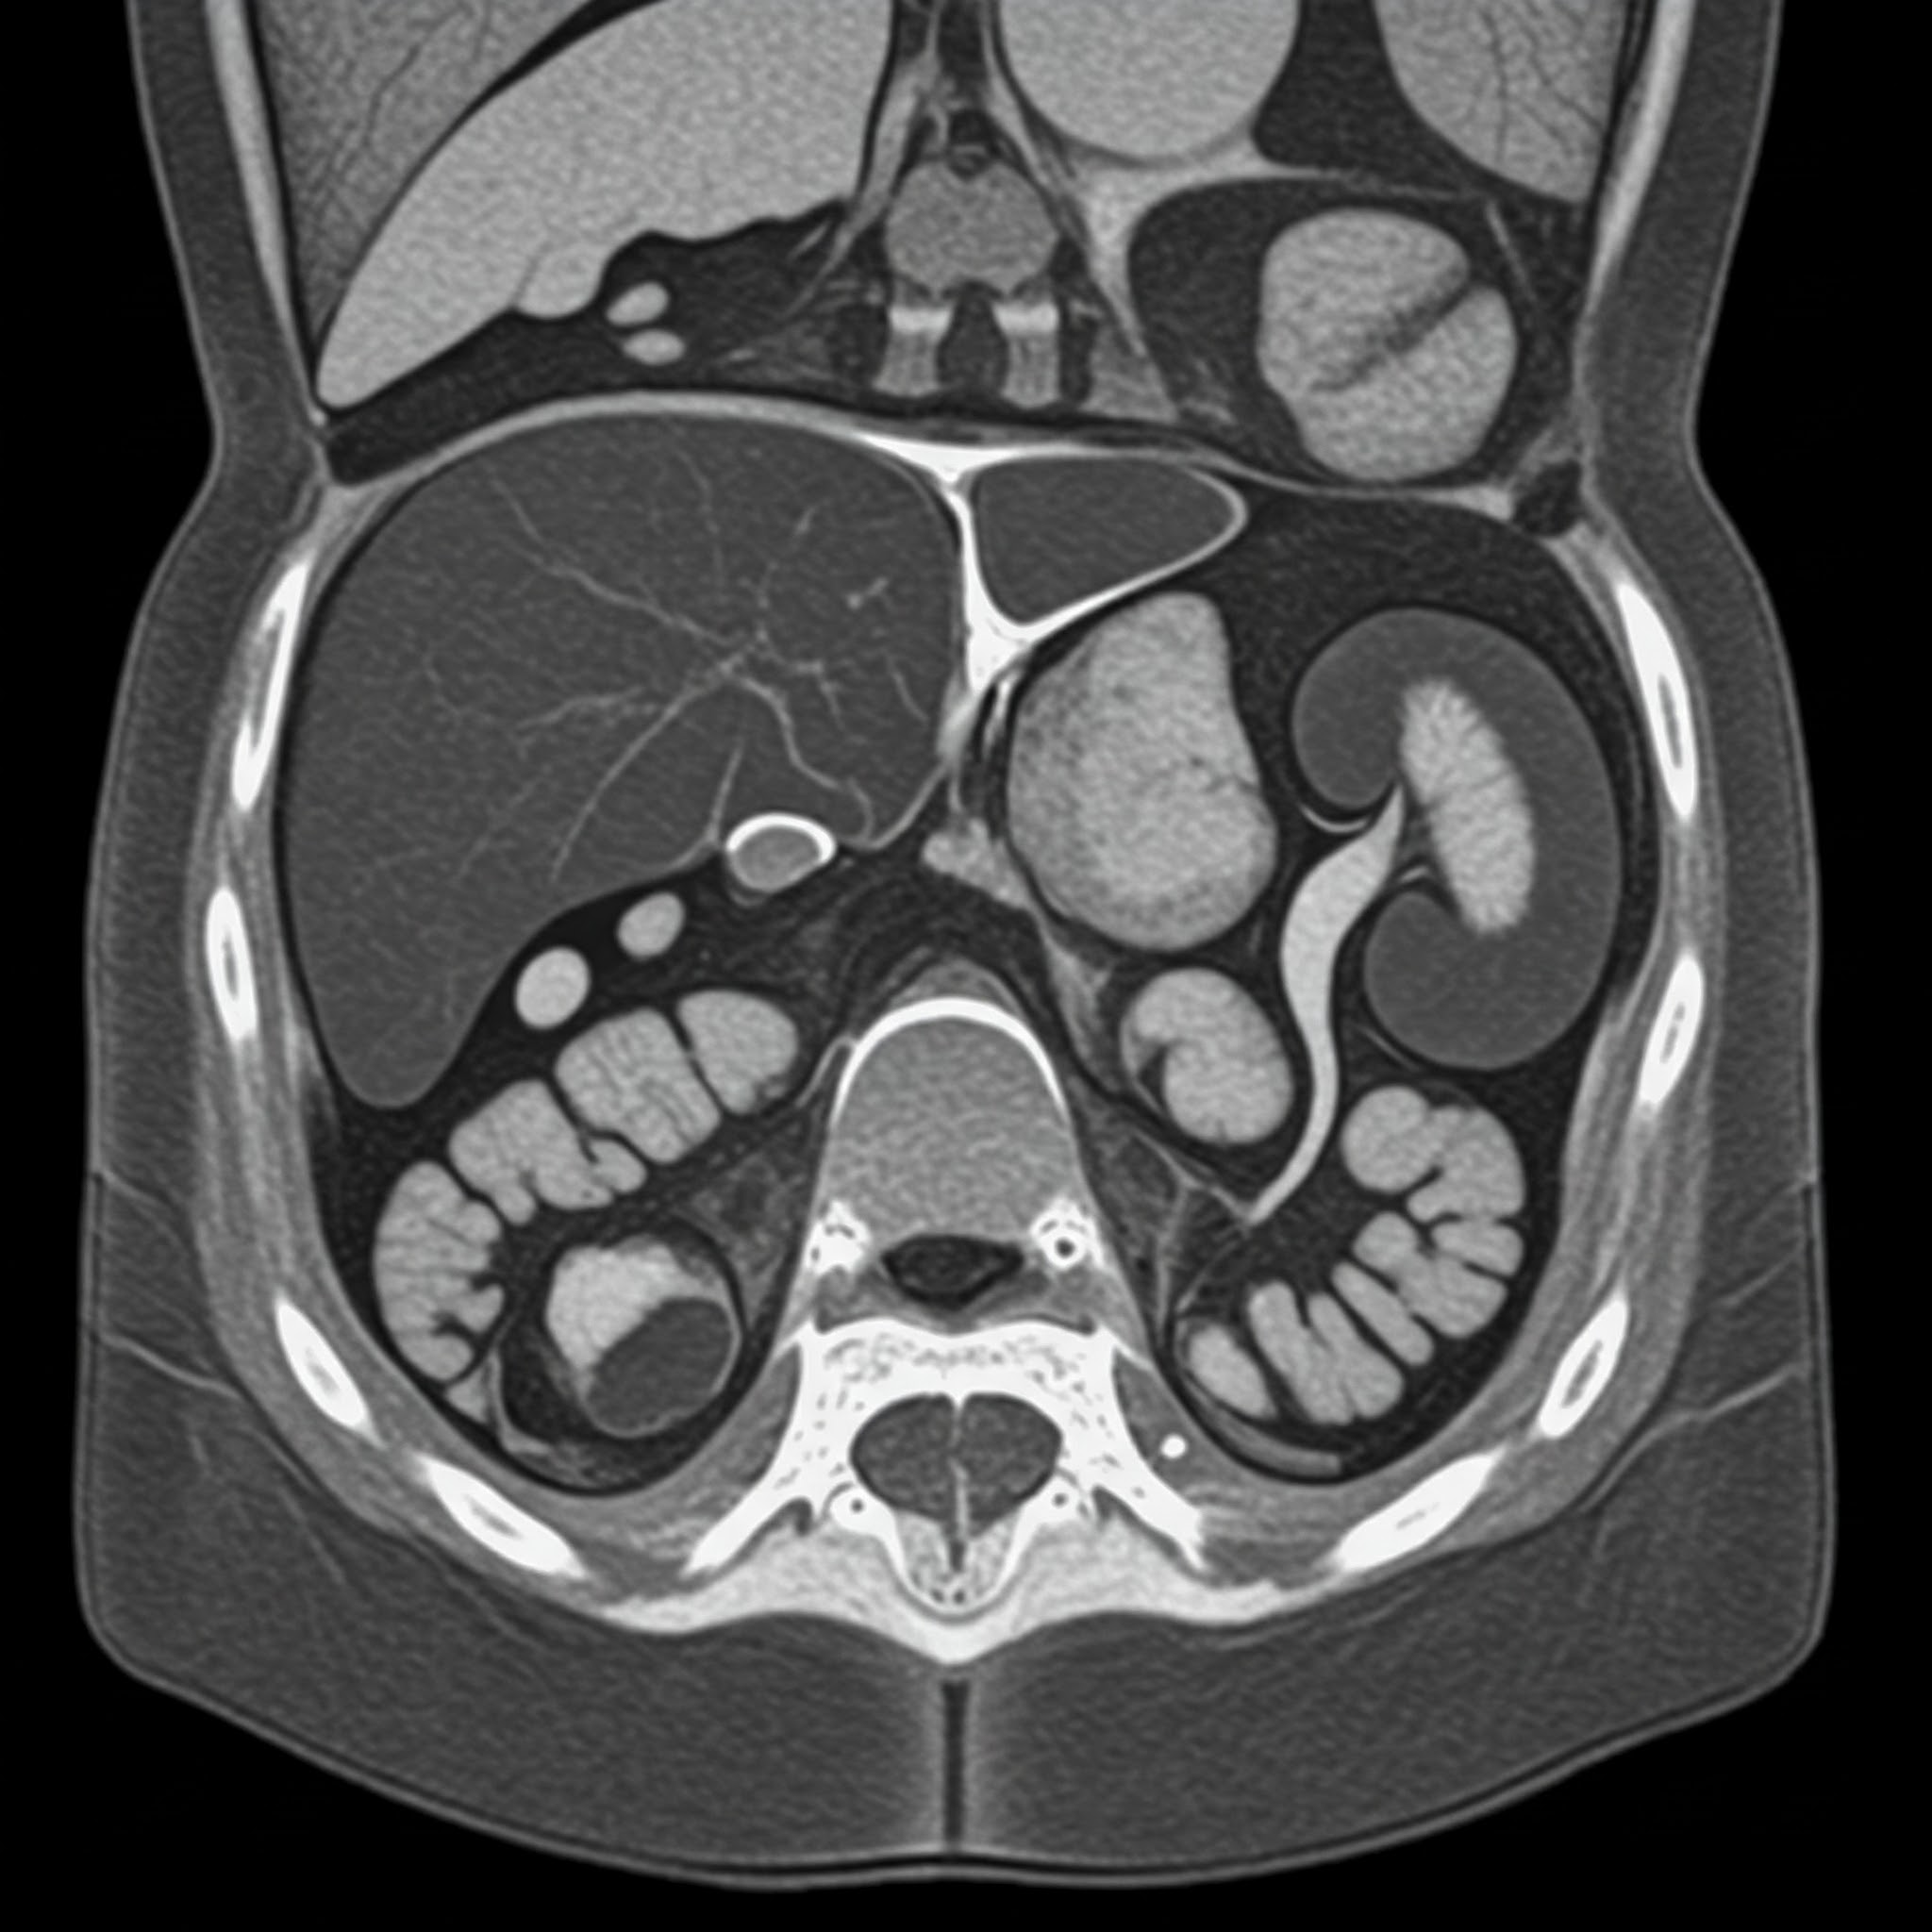

컴퓨터 단층 촬영(CT)은 현대 의학에서 질병 진단 및 치료 계획 수립에 필수적인 영상 검사입니다. 하지만 CT 촬영 시 발생하는 방사능 노출에 대한 우려도 적지 않습니다. 이 글에서는 안면 CT, 복부 CT 등 다양한 CT 촬영 시 발생하는 방사능 노출량과 안전한 CT 촬영을 위한 정보를 제공합니다.

CT 촬영 시 발생하는 방사능 노출량은 촬영 부위, 촬영 기기, 촬영 조건 등에 따라 달라집니다. 일반적으로 다음과 같습니다.

- 복부 CT: 약 10~20mSv